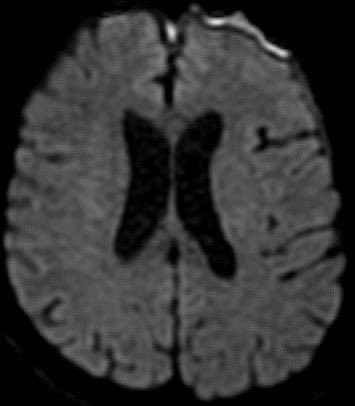

60 y/o with history of diabetes presents with progressive right proptosis, vision loss and confusion. What is the most likely diagnosis? 🧠

💡 Black Turbinate Sign has been reported as a finding highly suggestive of invasive fungal rhinosinusitis in immunocompromised patients

💡 Absent sinus mucosal enhancement is a 🔑 imaging feature as it implies invasion with vascular compromise and necrosis of the mucosa

The black turbinate sign is very specific in the appropriate setting though often not seen

💡 We must look for extra sinus invasion, particular intracranially, intraorbital, retromaxillary and other areas of absent mucosal enhancement to aid in the diagnosis

💡Benign turbinate nonenhancement can occur, look for:

1️⃣IMMUNOCOMPETENT host without clinical suspicion

2️⃣Improves over subsequent series

3️⃣Has preserved thin peripheral enhancement

4️⃣Often has thin internal septa

5️⃣Often occurs in the posterior aspect of the inferior turbinate